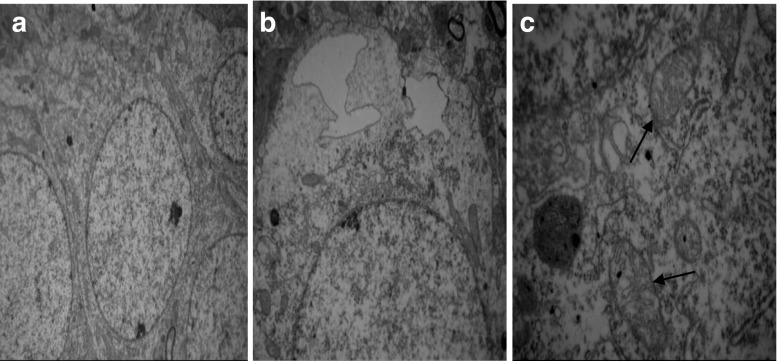

Under electron microscope, for H-MMC group, swelling and dissolution of Golgi complex were observed, along with endoplasmic reticulum expansion, mitochondria hypertrophy, and cytoplasmic edema (Fig. 6a–d). There were obvious signs of endoplasmic reticulum expansion and mild cytoplasmic edema in L-MMC group rats (Fig. 7a–c). Both of the MMC injected groups of rats showed organized hippocampal neurons, complete cell membrane, and normal mitochondria. No anomalous hippocampal dentate gyrus cells were observed in N-NaCl group (Fig. 8a–c).

Electron microscope images of L-MMC. (Transmission electron microscopy, A, ×40,000). a Hippocampal nerve cells arranged neatly and coated complete. b No obvious interstitial the cell edema. c Some mitochondria swelling (↑)

Fig. 8.

a–c Electron microscope images of N-Nacl. (Transmission electron microscopy, A, ×40,000). a hippocampal nerve cells arranged neatly and coated complete. b No obvious interstitial the cell edema. c Mitochondria, endoplasmic reticulum, and golgi complex organelles not seen obvious abnormity